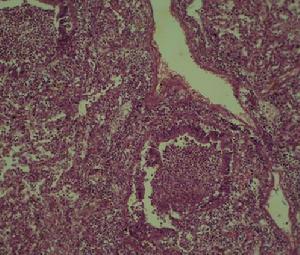

被巨細胞病毒侵害的肺病理生理

醫生診斷巨細胞病毒性肺炎實驗室檢查:周圍血白細胞減少。以呼吸道分泌物、唾液、尿液、子宮頸分泌物、肝、肺活檢標本接種至人胚成成纖維細胞培養基中可分離到巨細胞病毒。呼吸道分泌物和纖維支氣管鏡肺組織活檢標本內發現嗜酸性核內包涵體巨細胞,即能確診。測定血清的巨細胞病毒抗體,雙份血清抗體呈4倍或以上增長時,有助於診斷。